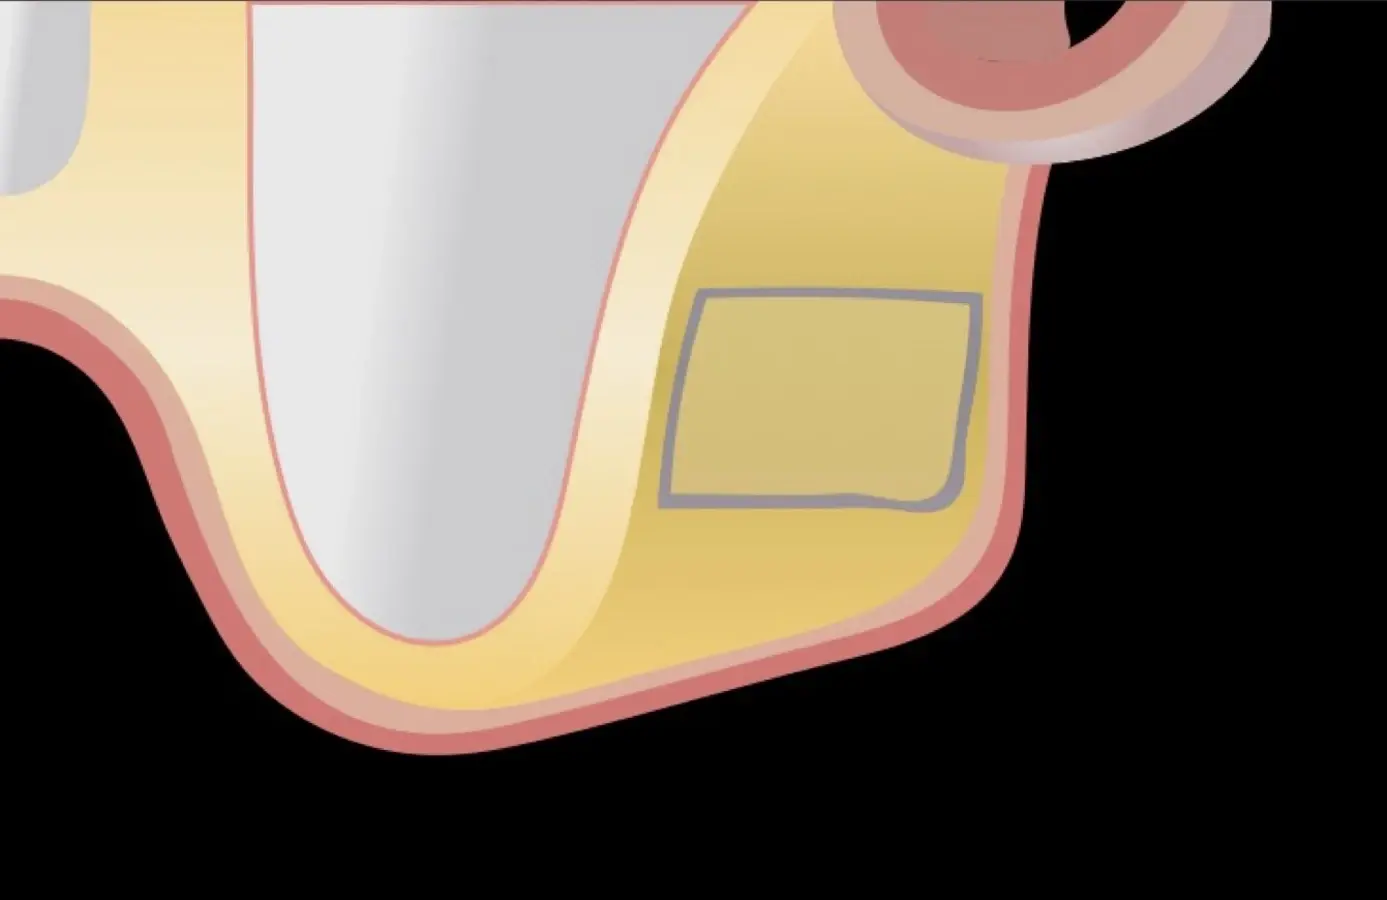

Figura 1. Incisión y levantamiento de colgajo a espesor total.

Figura 2. Espesor de la pared lateral (X), altura del reborde residual (Y), profundidad del seno maxilar (Z) y espesor de la membrana sinusal.

El tipo de inserto a ser utilizado dependerá del espesor de la pared ósea. Si la pared es menor a 0.5 mm, es mejor utilizar insertos de desgaste para prevenir la ruptura de la membrana de Schneider; si el espesor es mayor a 0.5 mm, se puede utilizar insertos de corte de espesor medio (Figura 3).

Figura 4. Diseño rectangular de la ventana lateral.